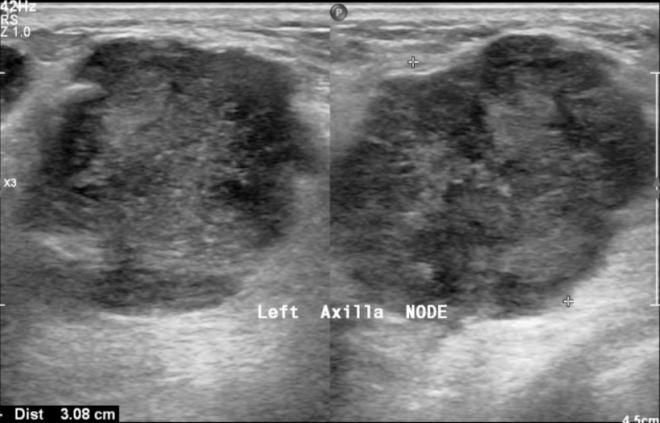

A 53 y old man was presented to our hospital with a progressively enlarging lump in his left breast with surface ulceration. He had multiple neurofibromas all over his body. Physical examination revealed a hard mass in the left breast with skin involvement and erythema of the skin. He underwent an ultrasound that revealed a large lobulated heterogeneous (fig. 1) wider-than-taller mass lesion at the 2 o'clock position in the periareolar region with posterior acoustic enhancement with pectoralis muscle infiltration and overlying skin thickening and ulceration (BIRAD V). Also, left axillary lymphadenopathy (fig. 2) was noted.

Fig. 2: Ultrasound picture showing left axillary lymphadenopathy